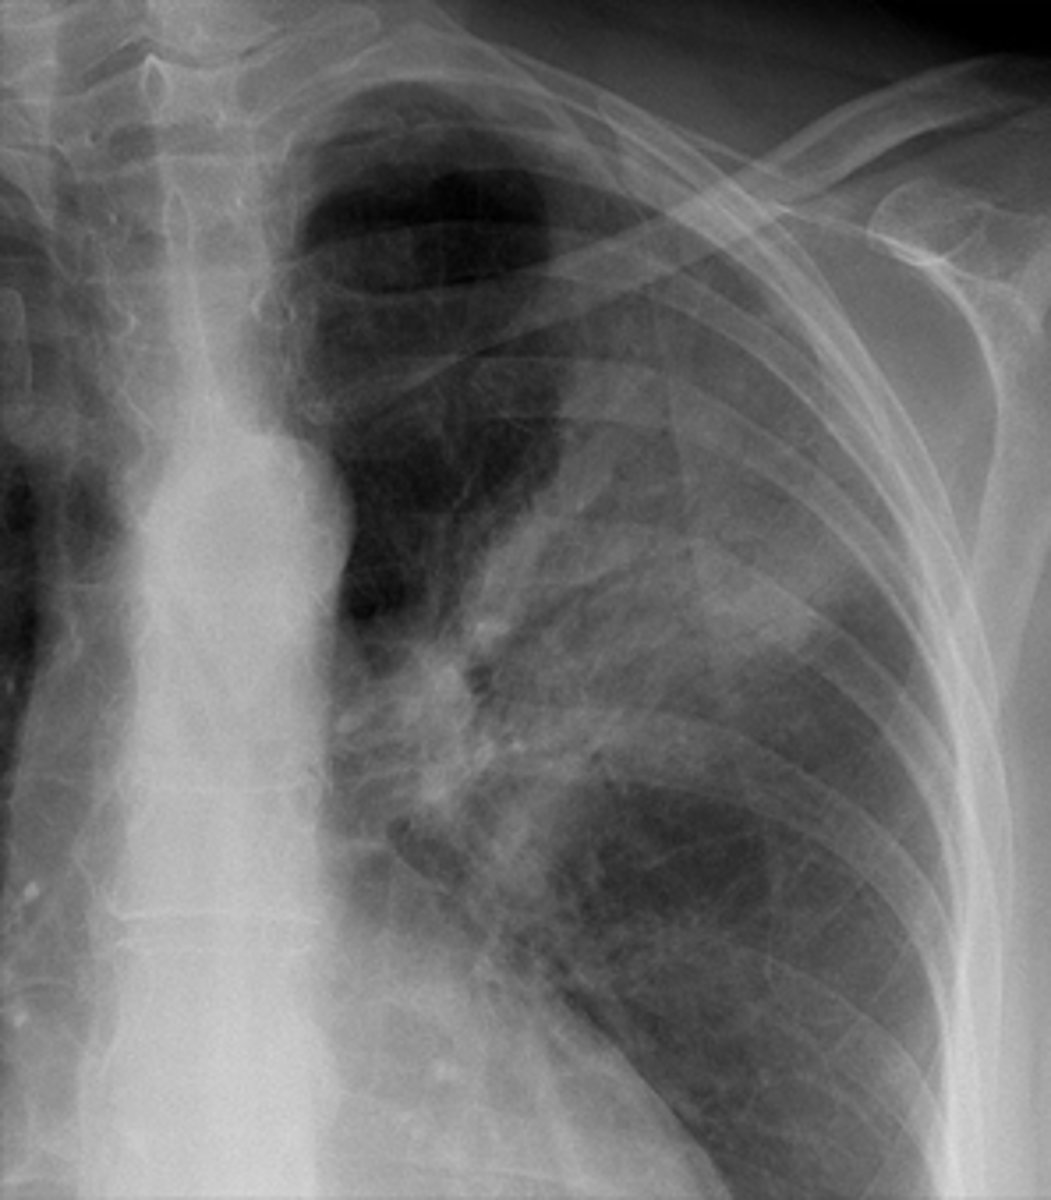

Pancoast tumor